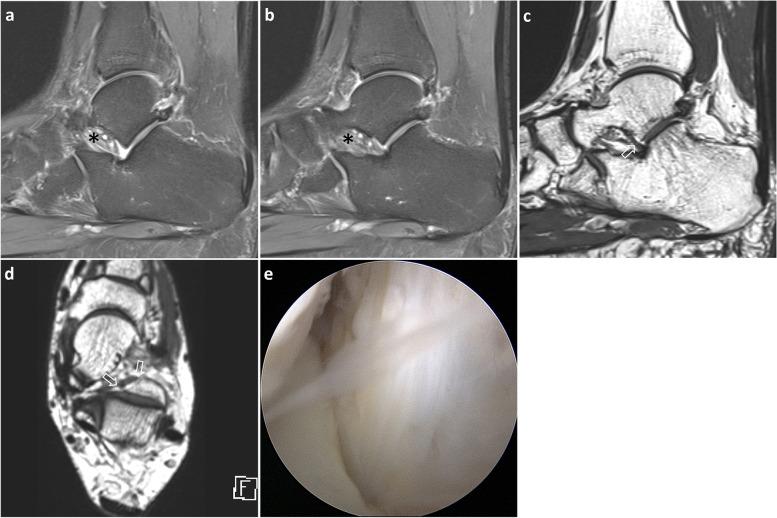

Interosseous ligament vertical segment (IOLV) and calcaneofibular ligament (CFL) have been reported to be important in stabilizing the subtalar joint. Unlike CFL, there is not much information regarding the comparison of MRI results with surgical evaluation of IOLV and the comparison between 2D and 3D MRI on IOLV evaluation. The feasibility of MRI in IOLV evaluation has yet to be reported. The purpose of this study was to evaluate the validity and reliability of MRI in IOLV tear detection via correlation with arthroscopic results. We also compared the diagnostic performance of 2D and 3D MR images.

In this retrospective study, 52 patients who underwent subtalar arthroscopy after ankle MRI were enrolled. Arthroscopic results confirmed IOLV tear in 25 cases and intact IOLV in 27 cases. Two radiologists independently evaluated the IOLV tears using only conventional 2D images, followed by isotropic 3D images, and comparison with arthroscopic results.

Isotropic 3D MRI was feasible for the assessment of IOLV tear prior to subtalar arthroscopy. Additional 3D sequences showed higher diagnostic accuracy compared with conventional 2D sequences in IOLV evaluation. Isotropic 3D sequences may be more valuable in detecting IOLV tear in case of tarsal sinus fat obliteration.